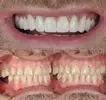

Zirconium Applications

Implant Treatment

Porcelain Applications

Laminate Veneer